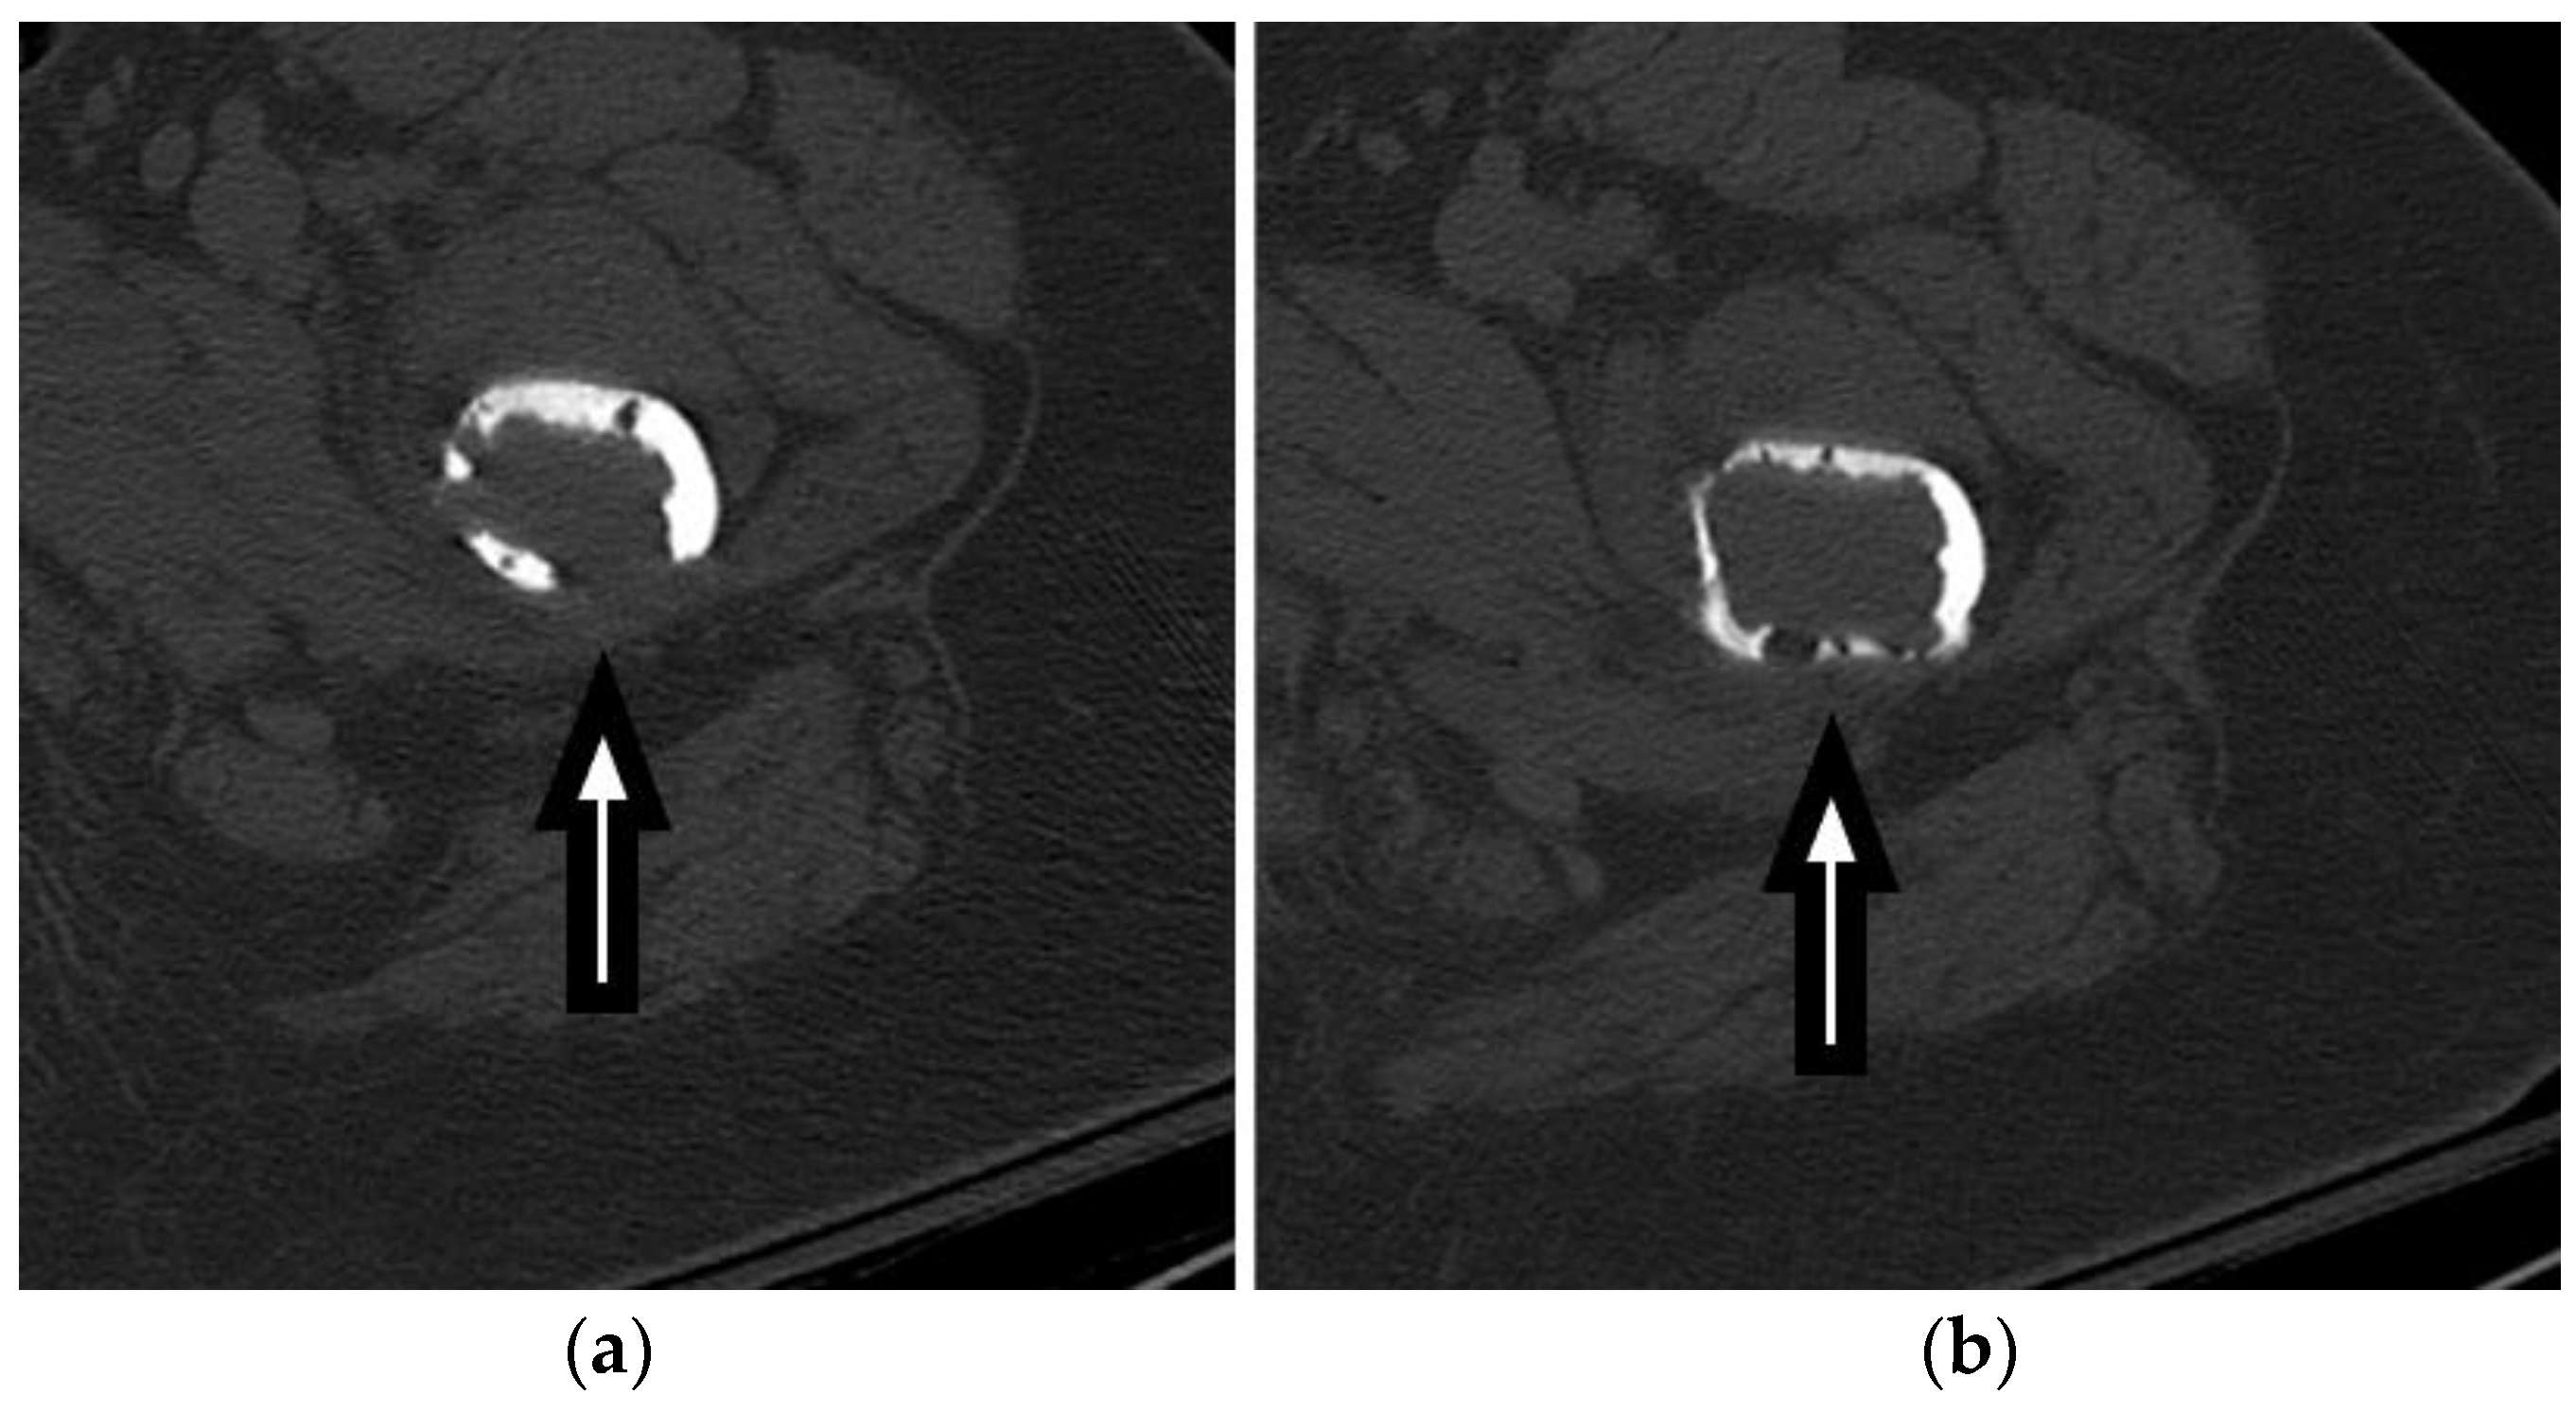

Figure 4. Axial (a,b), coronal (c), and sagittal (d) CT images show a destructive lytic lesion in the left proximal femoral metaphysis and diaphysis with cortical breakthrough both medially and posteriorly, concerning for pathologic fracture secondary to multiple myeloma.

CT imaging plays a vital role in the evaluation and management of FSFs by providing detailed information on the fracture pattern, displacement, intra-articular extension, and associated injuries, as seen in Figure 3 and Figure 4. Furthermore, Figure 5 demonstrates an example of a 3D reconstruction CT for surgical planning. The precise visualization of these key CT findings assists orthopedic surgeons in fracture classification, treatment planning, and surgical decision making. Incorporating CT imaging into the diagnostic workup of FSFs enhances the accuracy of diagnosis and contributes to improved patient outcomes.